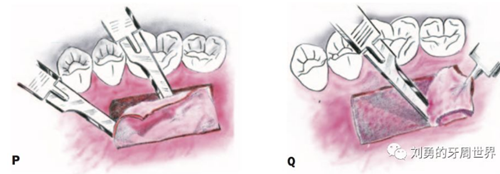

2、然后用15號刀片半厚瓣的方式取瓣,如下圖:

3、將移植瓣放濕鹽水紗布上保存。然后縫合供區(qū)止血(R)

4、將移植瓣去除脂肪腺體,放在鹽水紗布上修整確保表面光滑、厚度均勻(S、T)